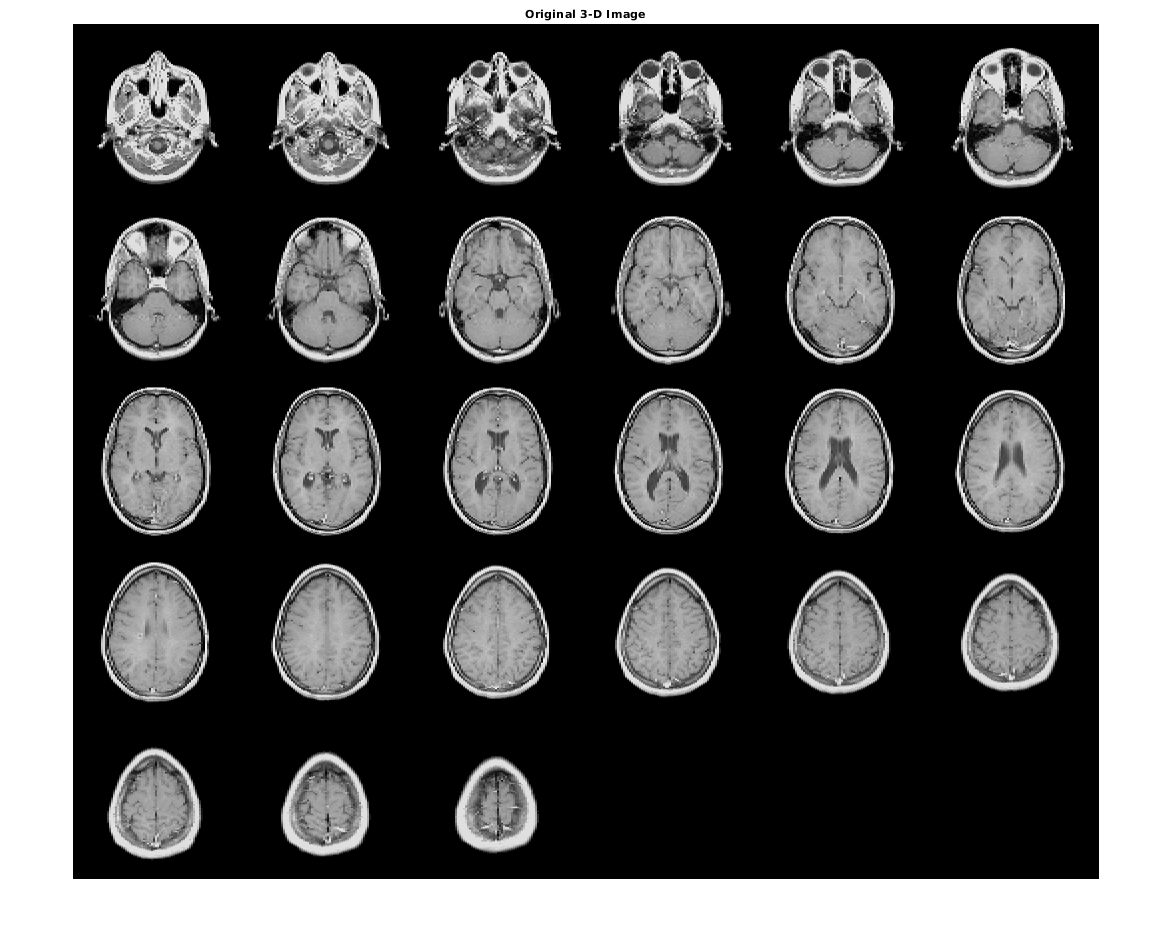

Загрузите полутоновое изображение N-D в рабочую область. Также загрузите полутоновое изображение, чтобы обеспечить ссылочную гистограмму.

load mri D

load mristack

Отобразите исходный объем как срезы.

figure

montage(D,'DisplayRange',[])

title('Original 3-D Image')